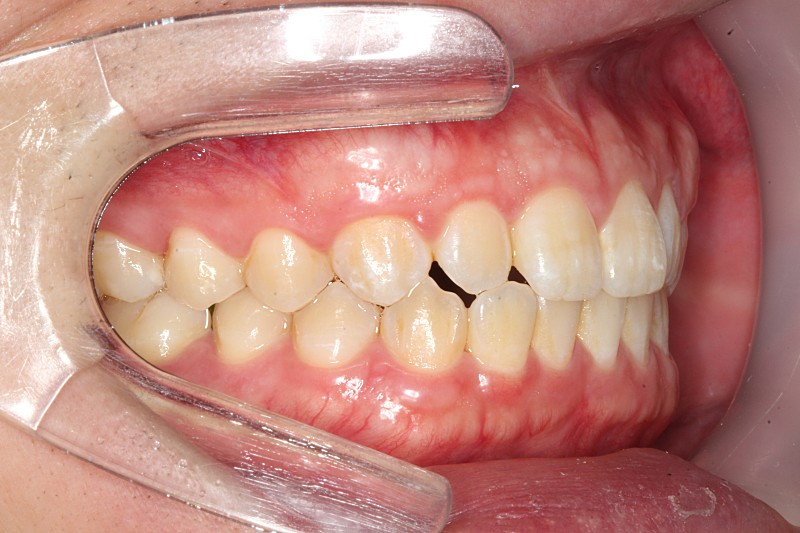

치아 앞니쪽에 반대교합이 있어서 분분교정할 생각인데 부분교정으로 치료가능해 보일까요?

앞니빼고 나머지는 괜찮아 보일까요?

윗니가 아랫니를 덮는 양또는 윗니가 앞으로 나온양이조금 적다고는 하는데 골격적 문제라 어쩔 수 없다는데 맞나요?

부분 교정으로도 어려워 보이며 전체 교정도 현재 증상을 개선하기가 쉽지 않아 보입니다. 워낙 다른 부위에 치열 상태는 나쁘지 않기 때문에 교정을 하더라도 현재 증상에 대한 개선이 어려울 수도 있어 보입니다. 또한 치열 배열 뿐만 아니라 골격적 문제가 동반되고 있어 골격적인 부분은 교정으로 수정할 수가 없습니다.

지금 정도의 골격적 부조화는 일반인들은 알아차리지 못하며 양악 등을 수술을 권하는 정도도 아닙니다.

사진상으로 보면 크게 문제가 있어보이지는 않습니다. 하지만, 기능상으로 문제가 있다면 교정을 하시거나 심미적개선을 원하신다면 교정을 하시면될것같아요.